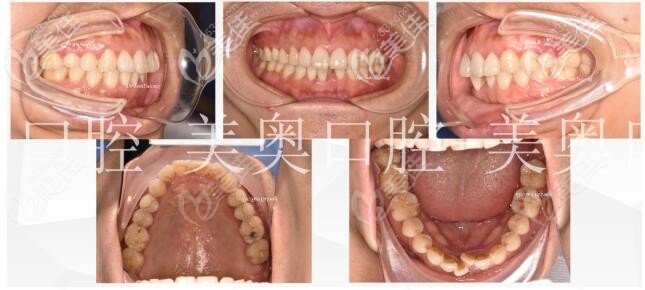

術前照片:

術后照片:

6個月后口內照,之前擁擠、參差不齊的牙齒現在已經有了明顯的改善,后續(xù)還要在下頜以舌側保持器進行固定,加強下頜前牙的穩(wěn)定性。